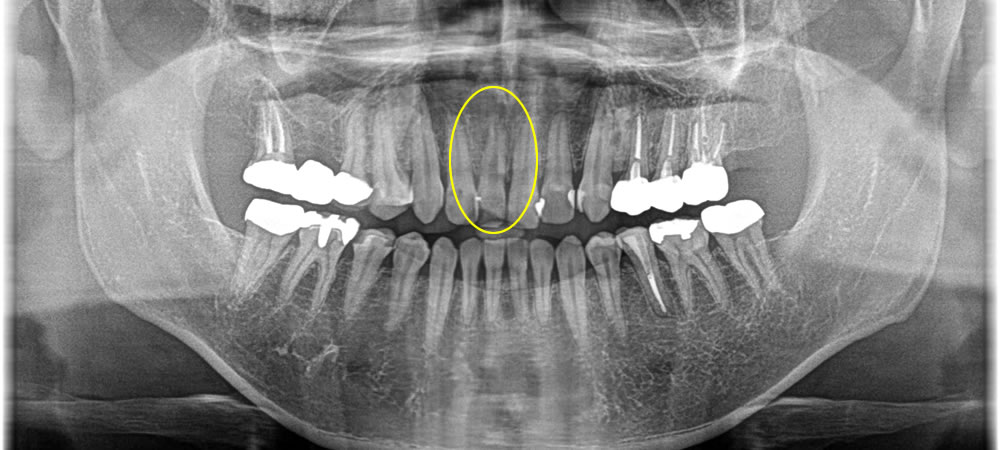

口腔内検査の結果、右上1番の歯に2~3度の動揺を確認。レントゲン画像にて、縦に破折線が見られ、それが原因で膿がたまり、歯槽骨を溶かしてしまっていたため、歯の動揺が生じていました。